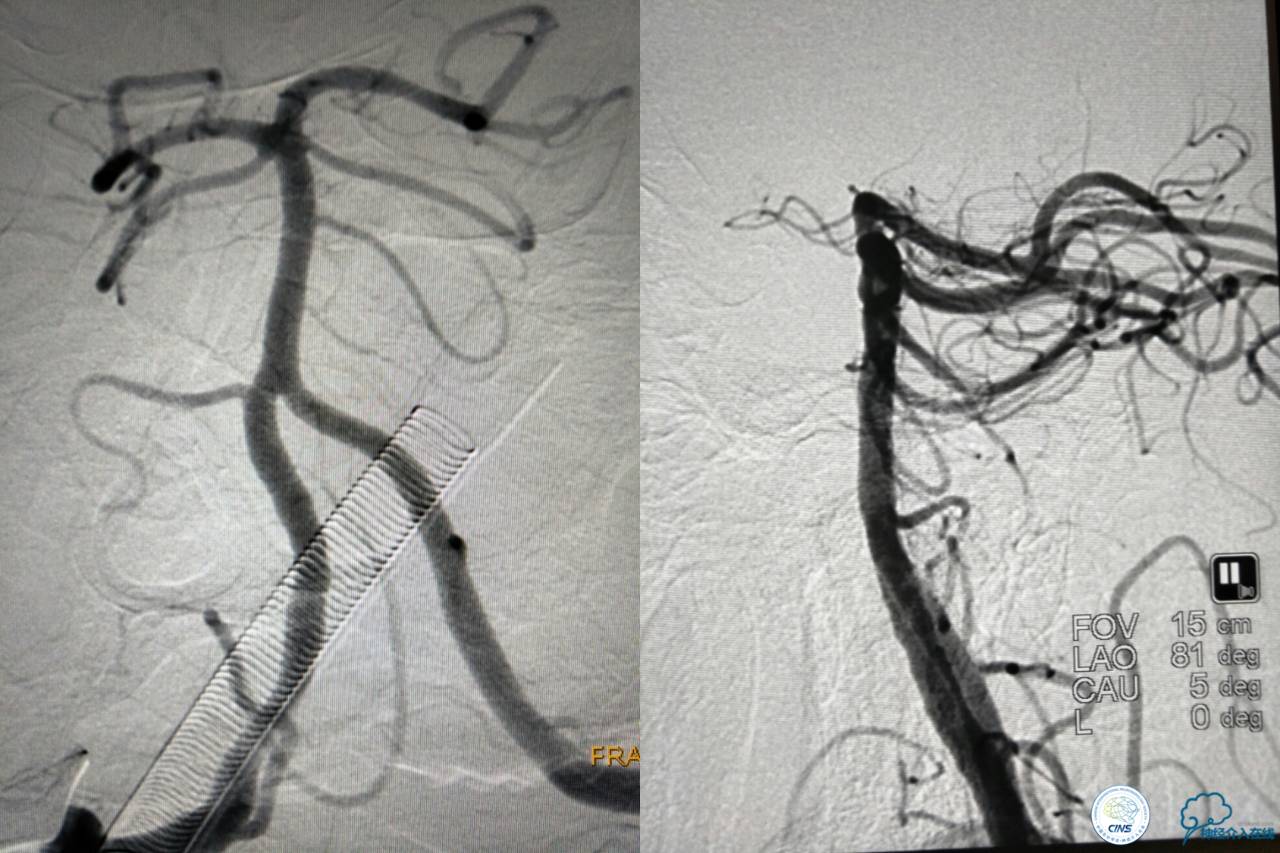

好大的血栓,支架释放后,血管无复流,拉一把!

没错,没看错!血管成功实现再通,术中取栓的栓子如下。

术后

术后生命体征平稳,成功撤呼吸机,肌力较前好转,复查头颅CT:

右侧丘脑高密度影,右侧枕叶可能也有梗死,祈祷慢慢恢复吧!